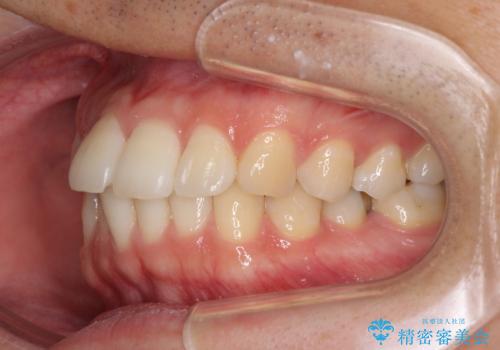

インビザライン・ライトによる矯正治療の後戻り改善

- 矯正治療の後戻りを気にして来院された患者様です。

後戻りは軽微でしたので、インビザライン・ライトにより矯正治療を行うこととしました。

再矯正後の後戻りを防ぐため、歯列排列後に、下顎前歯はワイヤーによる固定を行いました。

下顎前歯の歯列を動かないようにしておくことで、上顎前歯の後戻り防止にも効果を発揮します。